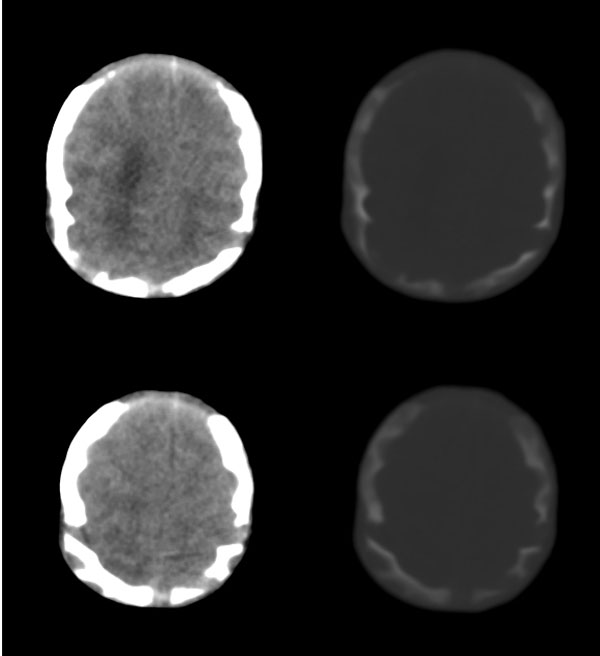

2天,枕部肿物

枕骨缺损,脑膜脑膨出。同时第4脑室挤压变形、闭塞,致使第3脑室、双侧侧脑室显著积水、扩张,过高的颅内压推挤脑实质,致使颅骨内板出现多而且深的脑回样压迹,脑细胞水肿,皮质、白质分界不清。

考虑先天性中脑水管梗阻,其以上脑室扩大。枕部脑膜脑膨出!

枕骨脑裂畸形伴脑膜脑膨出,双侧脑室扩张积水,第四脑室变窄致使双侧侧脑室及第三脑室积水,

枕骨缺损,脑膜脑膨出。同时第4脑室挤压变形、闭塞,致使第3脑室、双侧侧脑室显著积水、扩张.

脑积水——第4脑室挤压变形、闭塞,致使第3脑室、双侧侧脑室显著积水、扩张

颅骨内面凹陷——过高的颅内压推挤脑实质,过高的颅内压推挤脑实质,致使颅骨内板出现多而且深的脑回样压迹